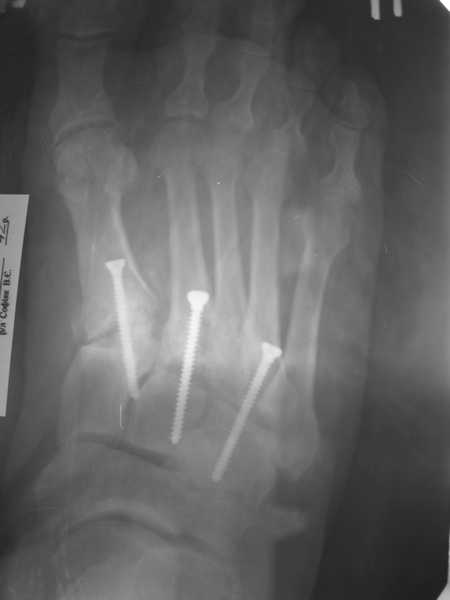

Обратился пациент, мужчина 42лет. для дальнейшего лечения. Травма 11.09., ДТП. 15.09 проведено оперативное лечение фиксаторами.)

(Блокирующий стержень левого бедра - статическая система. Открытое вправление вывиха в суставе Лисфранка и фиксация мет. фиксаторами.) D.S. Переломы диафиза и межмыщелковой области левого бедра, вывих в суставе Лисфранка правой стопы. Состояние после МОС. Через 6 нед. контрольная Ro,( снимки прилагаются).

По суставу Лисфранка :

1- 8 -9 нед . полный покой в гипсовой шине,а потом дозированная нагрузка.

2- Сейчас (на 7 нед.) пригипсовать каблук под пятку и давать дозированную нагрузку, и на 12 нед, одновременно с переводом статической системы в динамическую провести удаление фиксаторов из стопы.